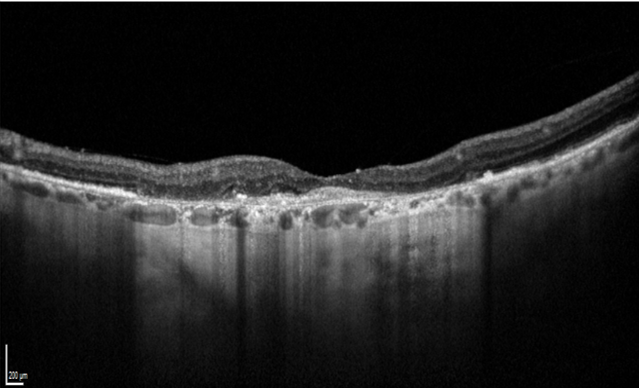

Elle se caractérise par le développement de petits vaisseaux gorgés de sang au centre de la macula. Ces vaisseaux peuvent saigner, et créer un gonflement de la rétine appelé « œdème maculaire », entrainant ainsi la mort des photos récepteurs.

Lors du bilan, l’acuité visuelle est mesurée par l’orthoptiste. Ensuite un OCT maculaire permet de mesurer l’épaisseur de la macula et scanner la rétine à la recherche de signes exsudatifs, inflammatoires, de néovaisseaux… Il est complété par le module OCT Angiographique (OCT-A). Ces mesures servent au diagnostique mais aussi à la surveillance de la DMLA.